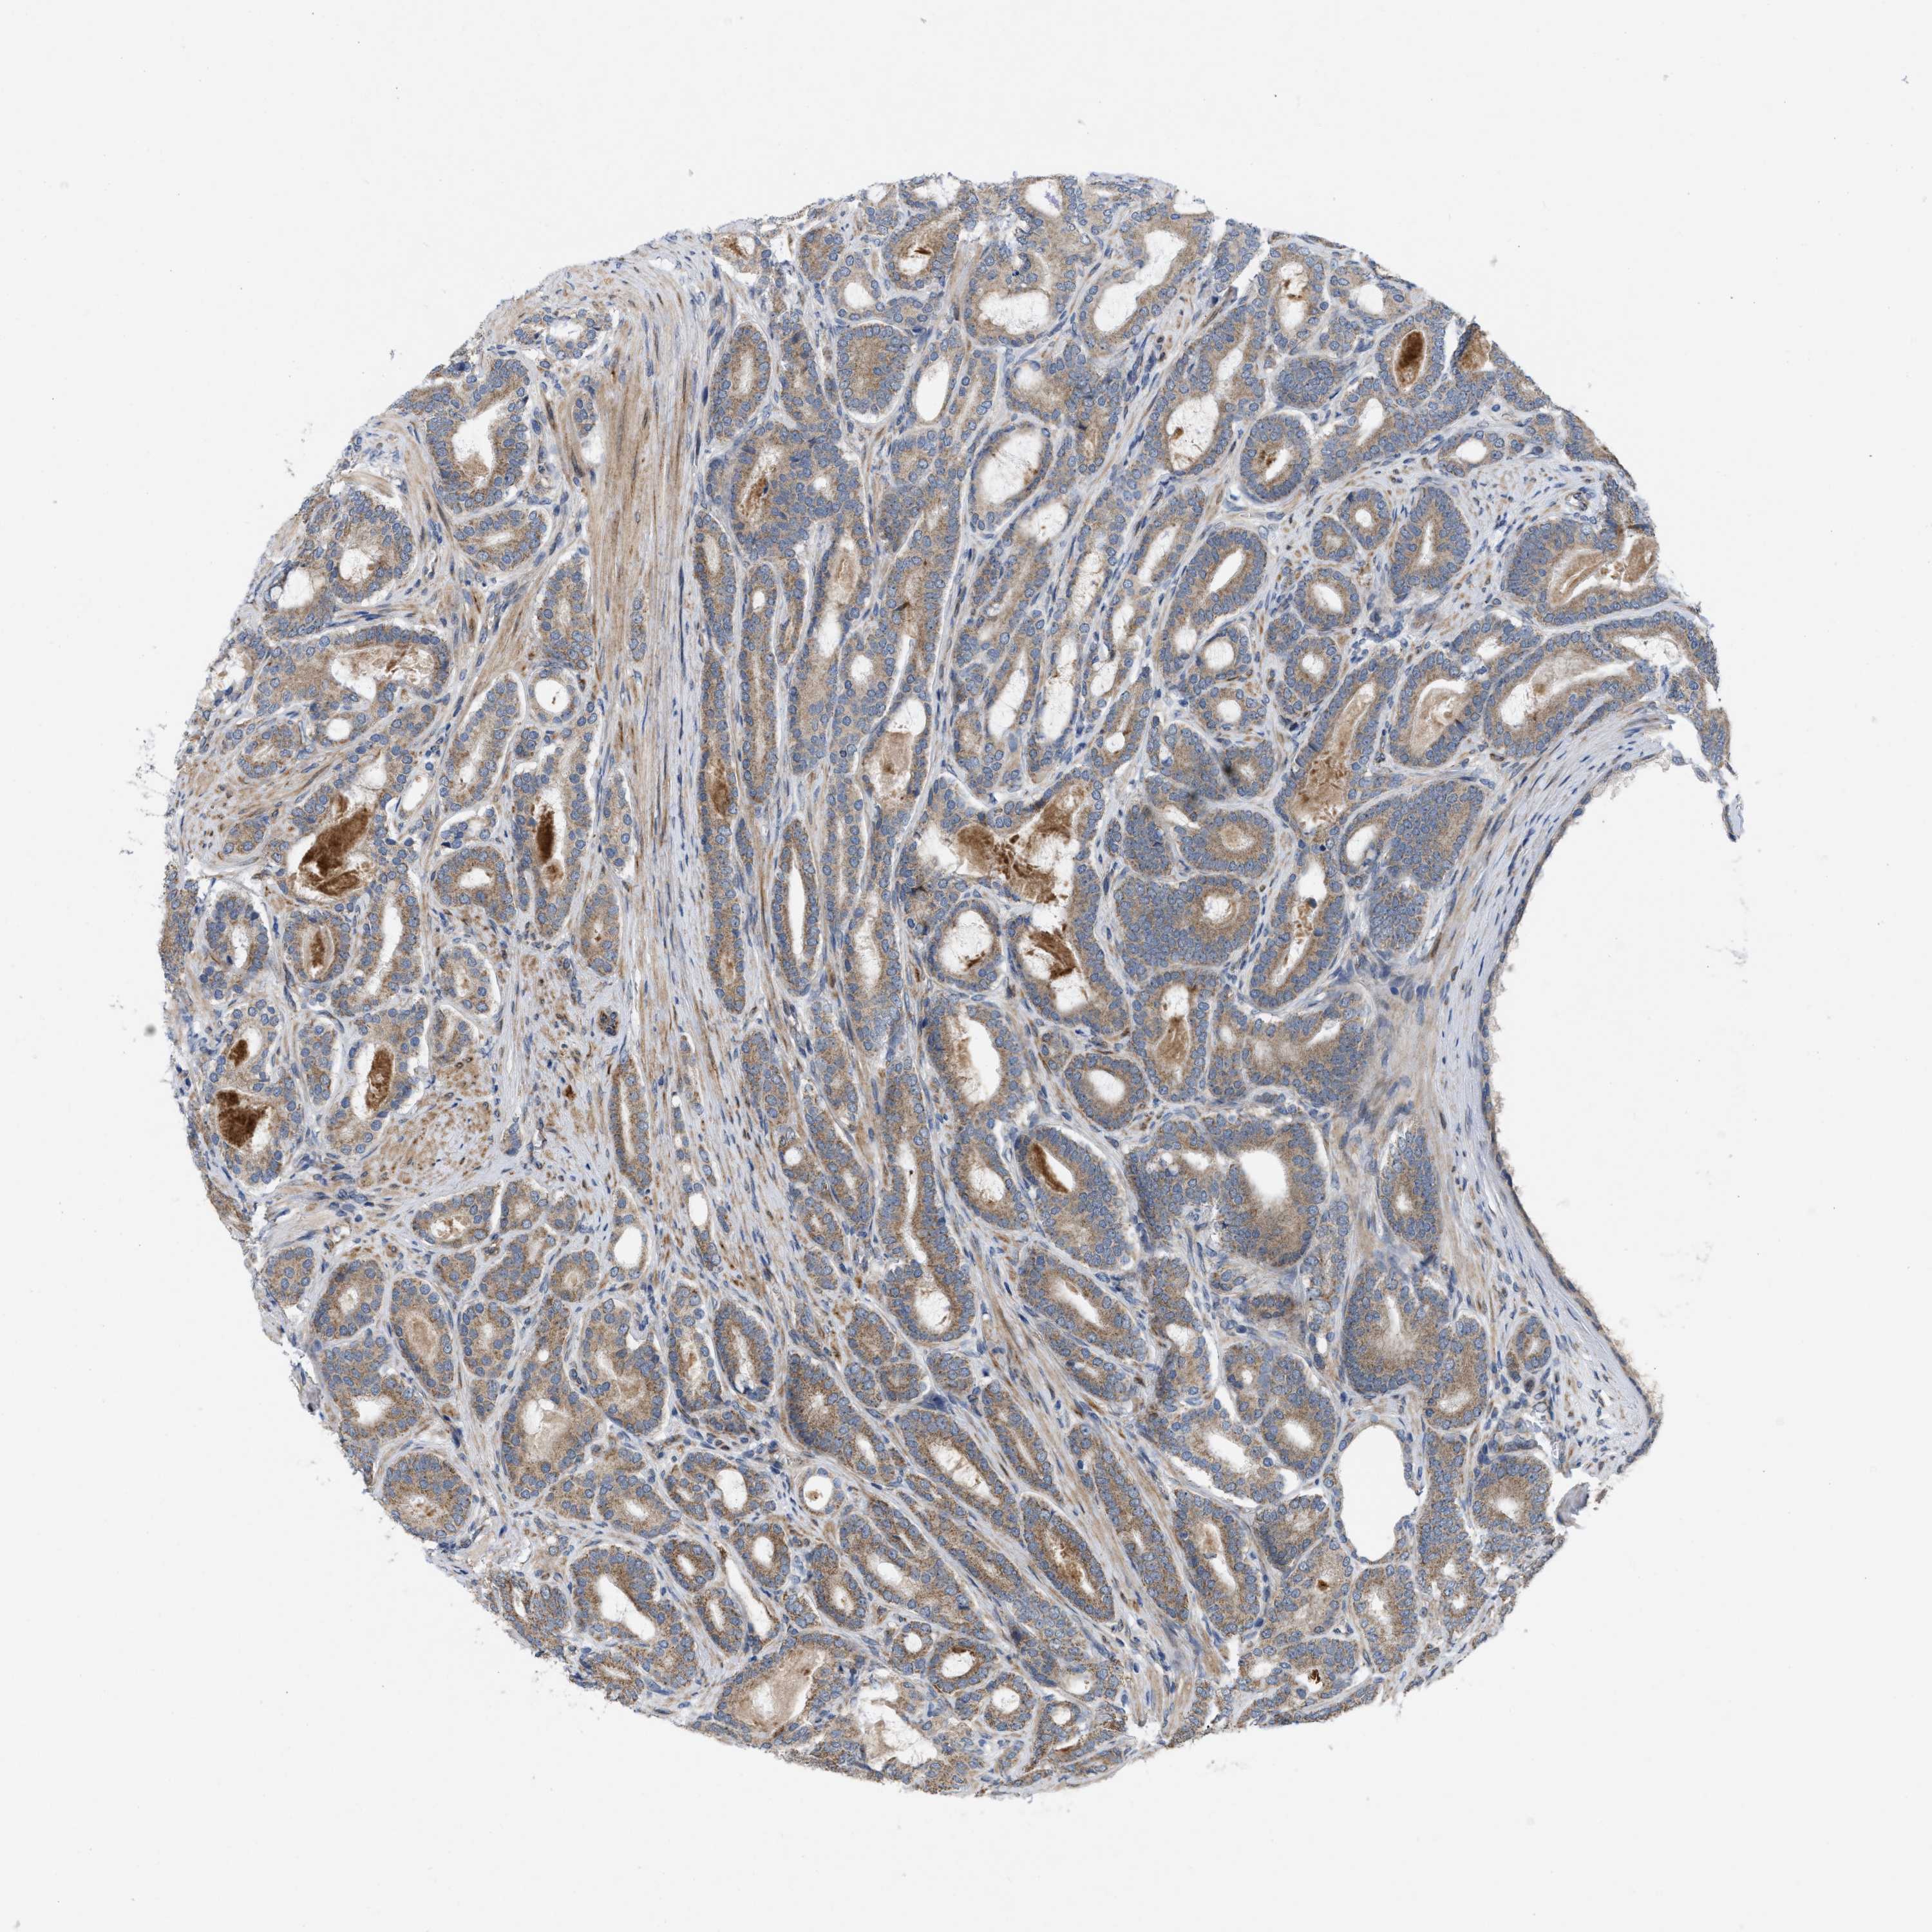

PROSTATE CANCER - Protein expressioni

A mouse-over function shows sample information and annotation data. Click on an image to view it in a full screen mode. Samples can be filtered based on level of antibody staining by selecting one or several of the following categories: high, medium, low and not detected. The assay and annotation is described here.

Note that samples used for immunohistochemistry by the Human Protein Atlas do not correspond to samples in the TCGA dataset.

Antibody stainingi

Antibody staining in the annotated cell types in the current human tissue is reported as not detected, low, medium, or high, based on conventional immunohistochemistry profiling in selected tissues. This score is based on the combination of the staining intensity and fraction of stained cells.

Each image is clickable and will lead to virtual microscopy that enables deeper exploration of all samples and also displays staining intensity scores, fraction scores and subcellular localization as well as patient and tissue information for each sample.

Antibody HPA019460

Staining

High

Medium

Low

Not detected

Intensity

Strong

Moderate

Weak

Negative

Quantity

>75%

75%-25%

<25%

None

Location

Nuclear

Cytoplasmic/membranous

Cytoplasmic/membranous,nuclear

Adenocarcinoma, High grade

Adenocarcinoma, Low grade